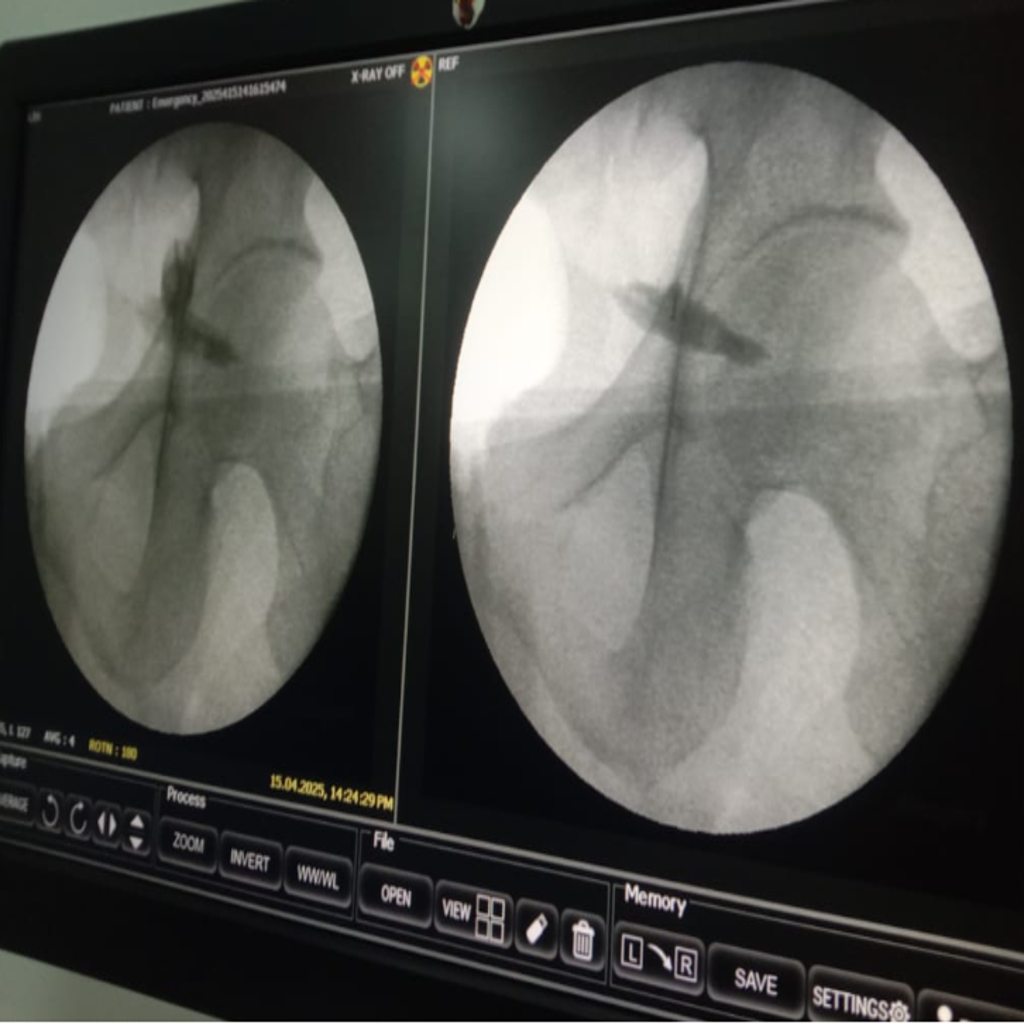

Fluoroscopy guided Injection for Piriformis Syndrome being carried out at Alleviate Pain Clinic, Bengaluru. Image Courtesy- Alleviate Pain Clinic

Image-guided precision treatments include:

- Lumbar facet joint injections for facet arthritis

- Medial branch blocks & radiofrequency ablation for chronic facet pain

- Sacroiliac joint injections for SI dysfunction

- Piriformis muscle injections (ultrasound-guided)

- Epidural or nerve root blocks for disc-related sciatica

These treatments:

- Target the exact pain generator

- Reduce medication dependence

- Avoid surgery in most cases